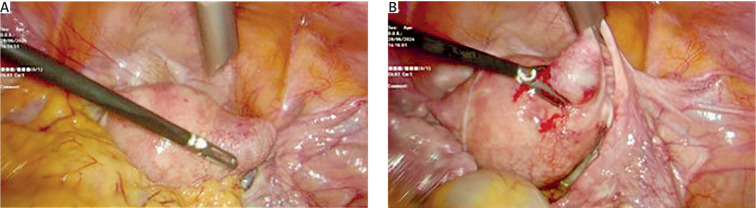

Interstitial pregnancy (IP) is a rare kind of tubal pregnancy, which occurs in 2-4% of all ectopic pregnancies. It occurs as a result of implantation of the gestational sac in the proximal intramural part of the fallopian tube. Risk factors include the following: pregnancy conceived after assisted reproductive technologies, ipsilateral salpingectomy, previous ectopic pregnancy, congenital tubal and uterine malformations, pelvic inflammatory disease, and the presence of an intrauterine device. Given the rare and complex nature of interstitial pregnancies, diagnosis and management are difficult. Transvaginal ultrasound is the most specific instrumental method for early diagnosis that can decrease possible complications, such as rupture, severe haemorrhage, and risk of future infertility in the case of misdiagnosis. There are various surgical and non-surgical methods for the treatment of interstitial pregnancy. The method of choice depends on gestational age, whether the pregnancy is intact or ruptured, and the patient's desire for future fertility. However, surgery is still the main option for the treatment of IP because it offers definitive treatment. Generally, complicated IP is associated with high rate of mortality due to delayed diagnosis and treatment. We present a case report related to a multiparous woman with amenorrhoea and ultrasound findings corresponding to sonographic criteria for interstitial pregnancy. Laparoscopy was performed, which confirmed the diagnosis. Bilateral salpingectomy and right cornual resection were performed because the patient had no intention for future pregnancies.